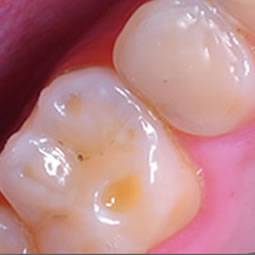

El Investigador José Córdova y Erich Astudillo de la Universidad de Chile (y fundador de Top Tech Innovaciones SpA) descubrió una nueva molécula que mata a la bacteria Streptococcus mutans, siempre conocido por ser responsable de descomponer los azúcares de los alimentos en el la boca y dejando tras de sí el ácido láctico que corroe el esmalte dental que lleva a la decadencia. La nueva molécula que llaman Keep32 se ha encontrado para matar las bacterias en contacto.

Con los años muchos productos han llegado con el objetivo de aliviar la plaga de la caries dental, las caries y, a veces la pérdida de los dientes, pero aparte de la introducción de flúor en el agua potable, no se ha logrado mucho. Si las afirmaciones hechas por este nuevo equipo resulta cierto, sin embargo, que podría anunciar una marca de las cuencas hidrográficas para librar al mundo de la caries dental, así como ayudar a mejorar el estado general de salud de millones de personas y la inflamación que se produce como resultado que en los últimos años veces se ha asociado a muchos otros problemas de salud en todo el cuerpo, incluyendo ataques al corazón e incluso demencia.